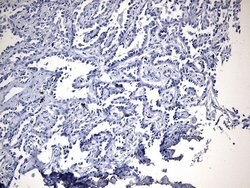

EGFR L858R Mouse anti-Human, Clone: UMAB234, lyophilized, UltraMAB™

EGFR (Epidermal growth factor receptor, HER1, ErbB1) is encoded by the EGFR gene located on chromosome 7 in humans. EGFR belongs to the HER/ERbB family of proteins that includes three other receptor tyrosine kinases, ERbB2, ERbB3, ERbB4. EGFR is a transmembrane receptor and binding of its cognate ligands such as EGF (Epidermal Growth Factor) and TGF alpha (Transforming Growth Factor alpha) to the extracellular domain leads to EGFR dimerization followed by autophosphorylation of the tyrosine residues in the cytoplasmic domain. Phosphorylation of EGFR at certain residues is also mediated by Src-non-receptor kinase. EGFR activation signals multiple downstream signaling cascades such as the Ras - ERK, PI3-K - Akt, Jak - STAT and PKC pathways that help in growth and proliferation of cells. Phosphorylation of EGFR at Y1086 specifically allows binding of the adaptor protein GRB2, leading to activation of the MAPK pathway. Upon receptor activation and signaling, EGFR is endocytosed and targeted for degradation or recycling. Mutations in the EGFR gene are associated with lung cancer and multiple alternatively spliced transcript variants encode different protein isoforms of EGFR have been found. Increased production or activation of EGFR has been associated with poor prognosis in a variety of tumors. Moreover, EGFR overexpression is observed in tumors of the head and neck, brain, bladder, stomach, breast, lung, endometrium, cervix, vulva, ovary, esophagus, stomach and in squamous cell carcinoma. This product is specific for EGFR (mutant L858R).Specifications

| Immunohistochemistry (Paraffin) | |

| Synthetic peptide around the L858R mutation region of the human EGFR conjugated to KLH | |